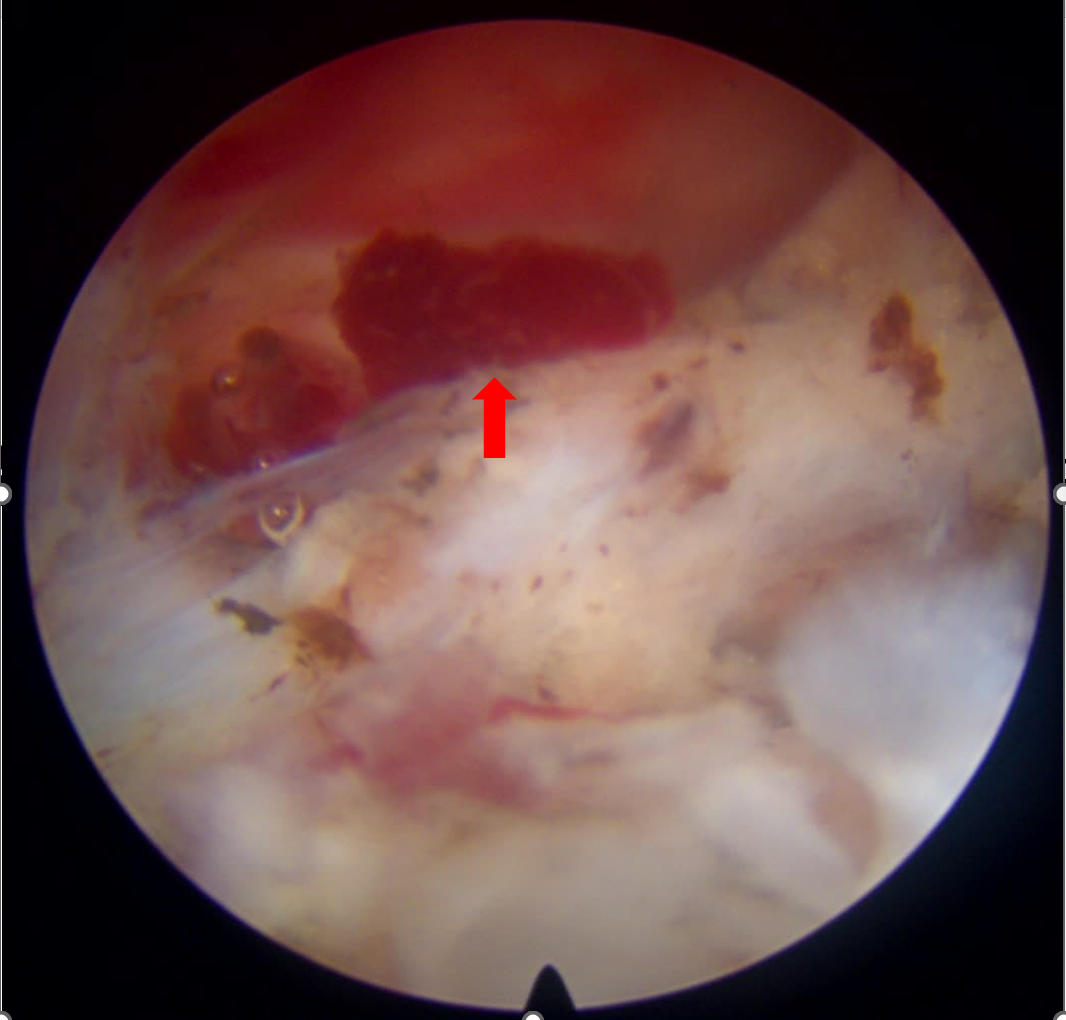

术中,镜下显示:小吴的椎管内硬膜外存在明显血肿,排除脱出髓核和肿瘤的可能。医疗团队在内镜视野下,小心翼翼地将压迫脊髓神经的血凝块全部清除,整个过程出血量少,创伤小。

术前血肿压迫

术中解除压迫

术后取出血肿